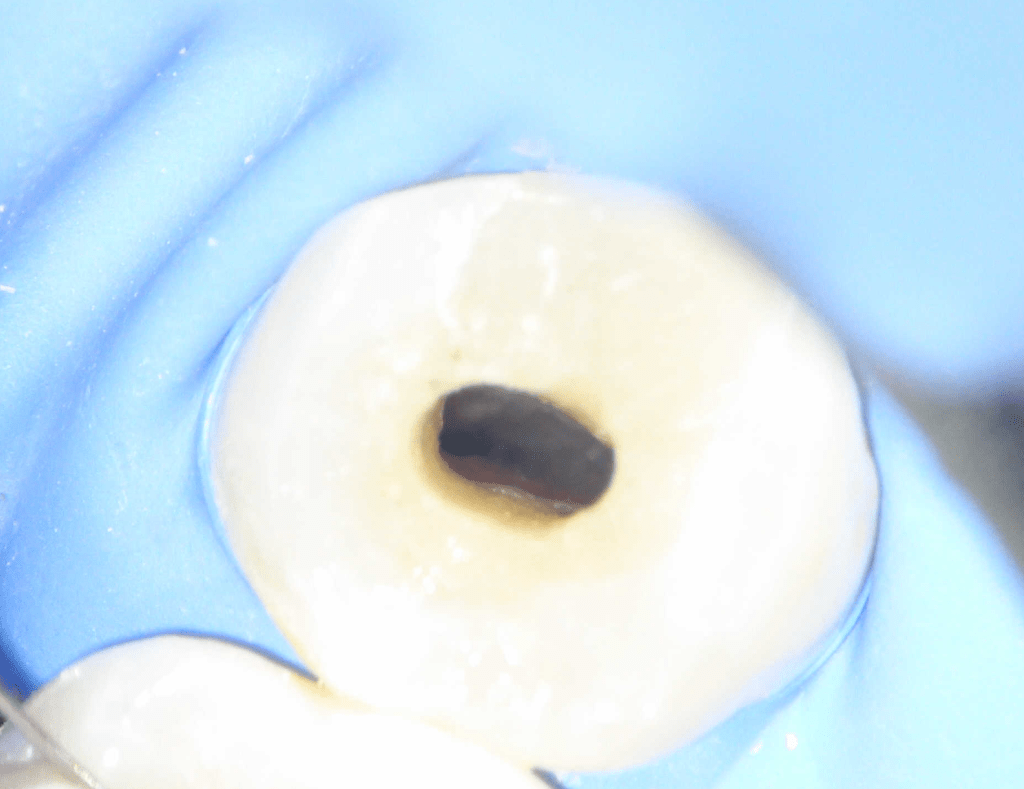

Fisura, remoción amalgama para explorar